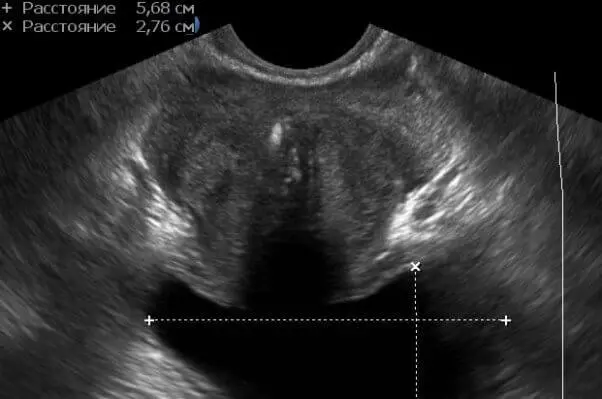

Мал. 4 Ділянки кальцинації центральної і парауретральной зон з щільною акустичної тінню.